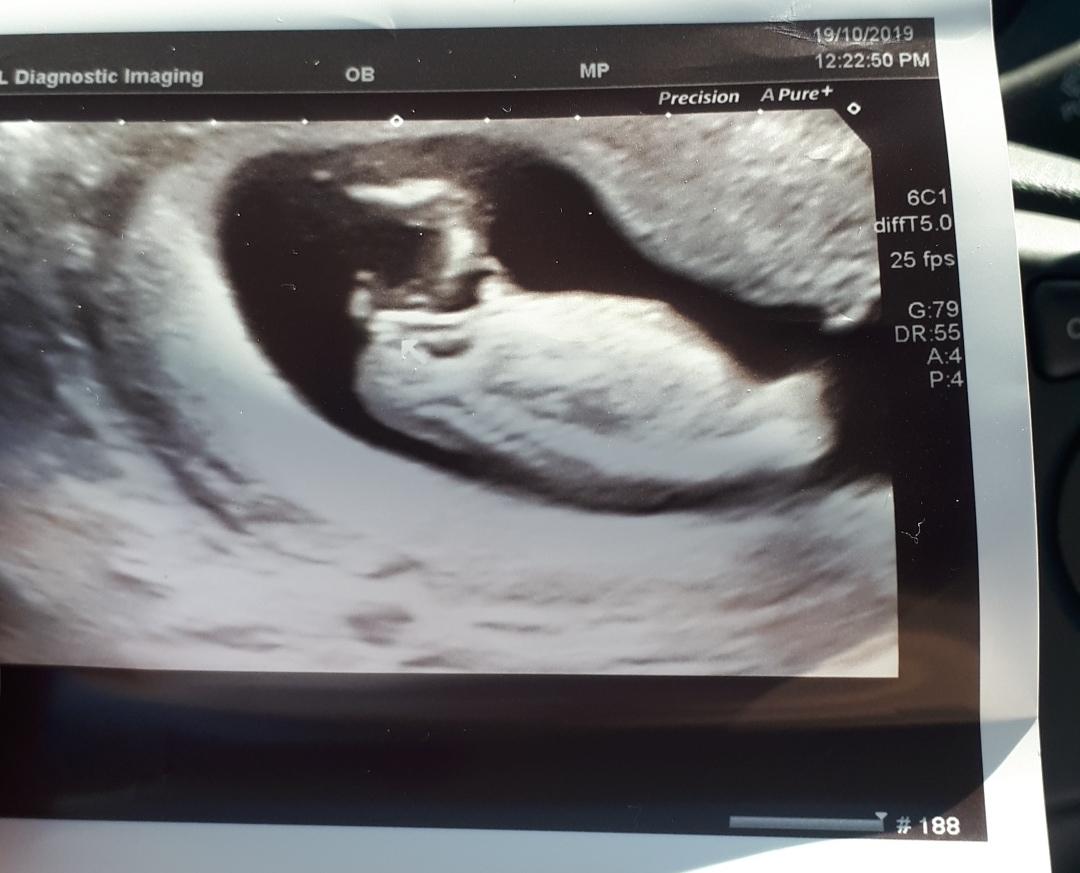

I sent my 13+3 ultrasound to the Nubologosts. I thought for sure I saw stacking and put it in my mind that its a boy...

Well, they sent it back and it says 98% GIRL!!!!!!!! Is this a joke???? I'm sitting here balling my eyes out. Could it be true? Please, ease my mind!